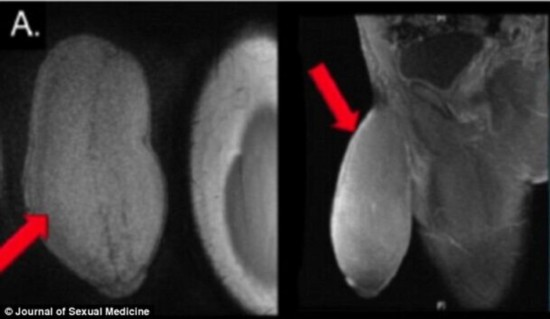

爱尔兰发情公牛交配过猛致阴茎折断

550x365 - 61KB - JPEG